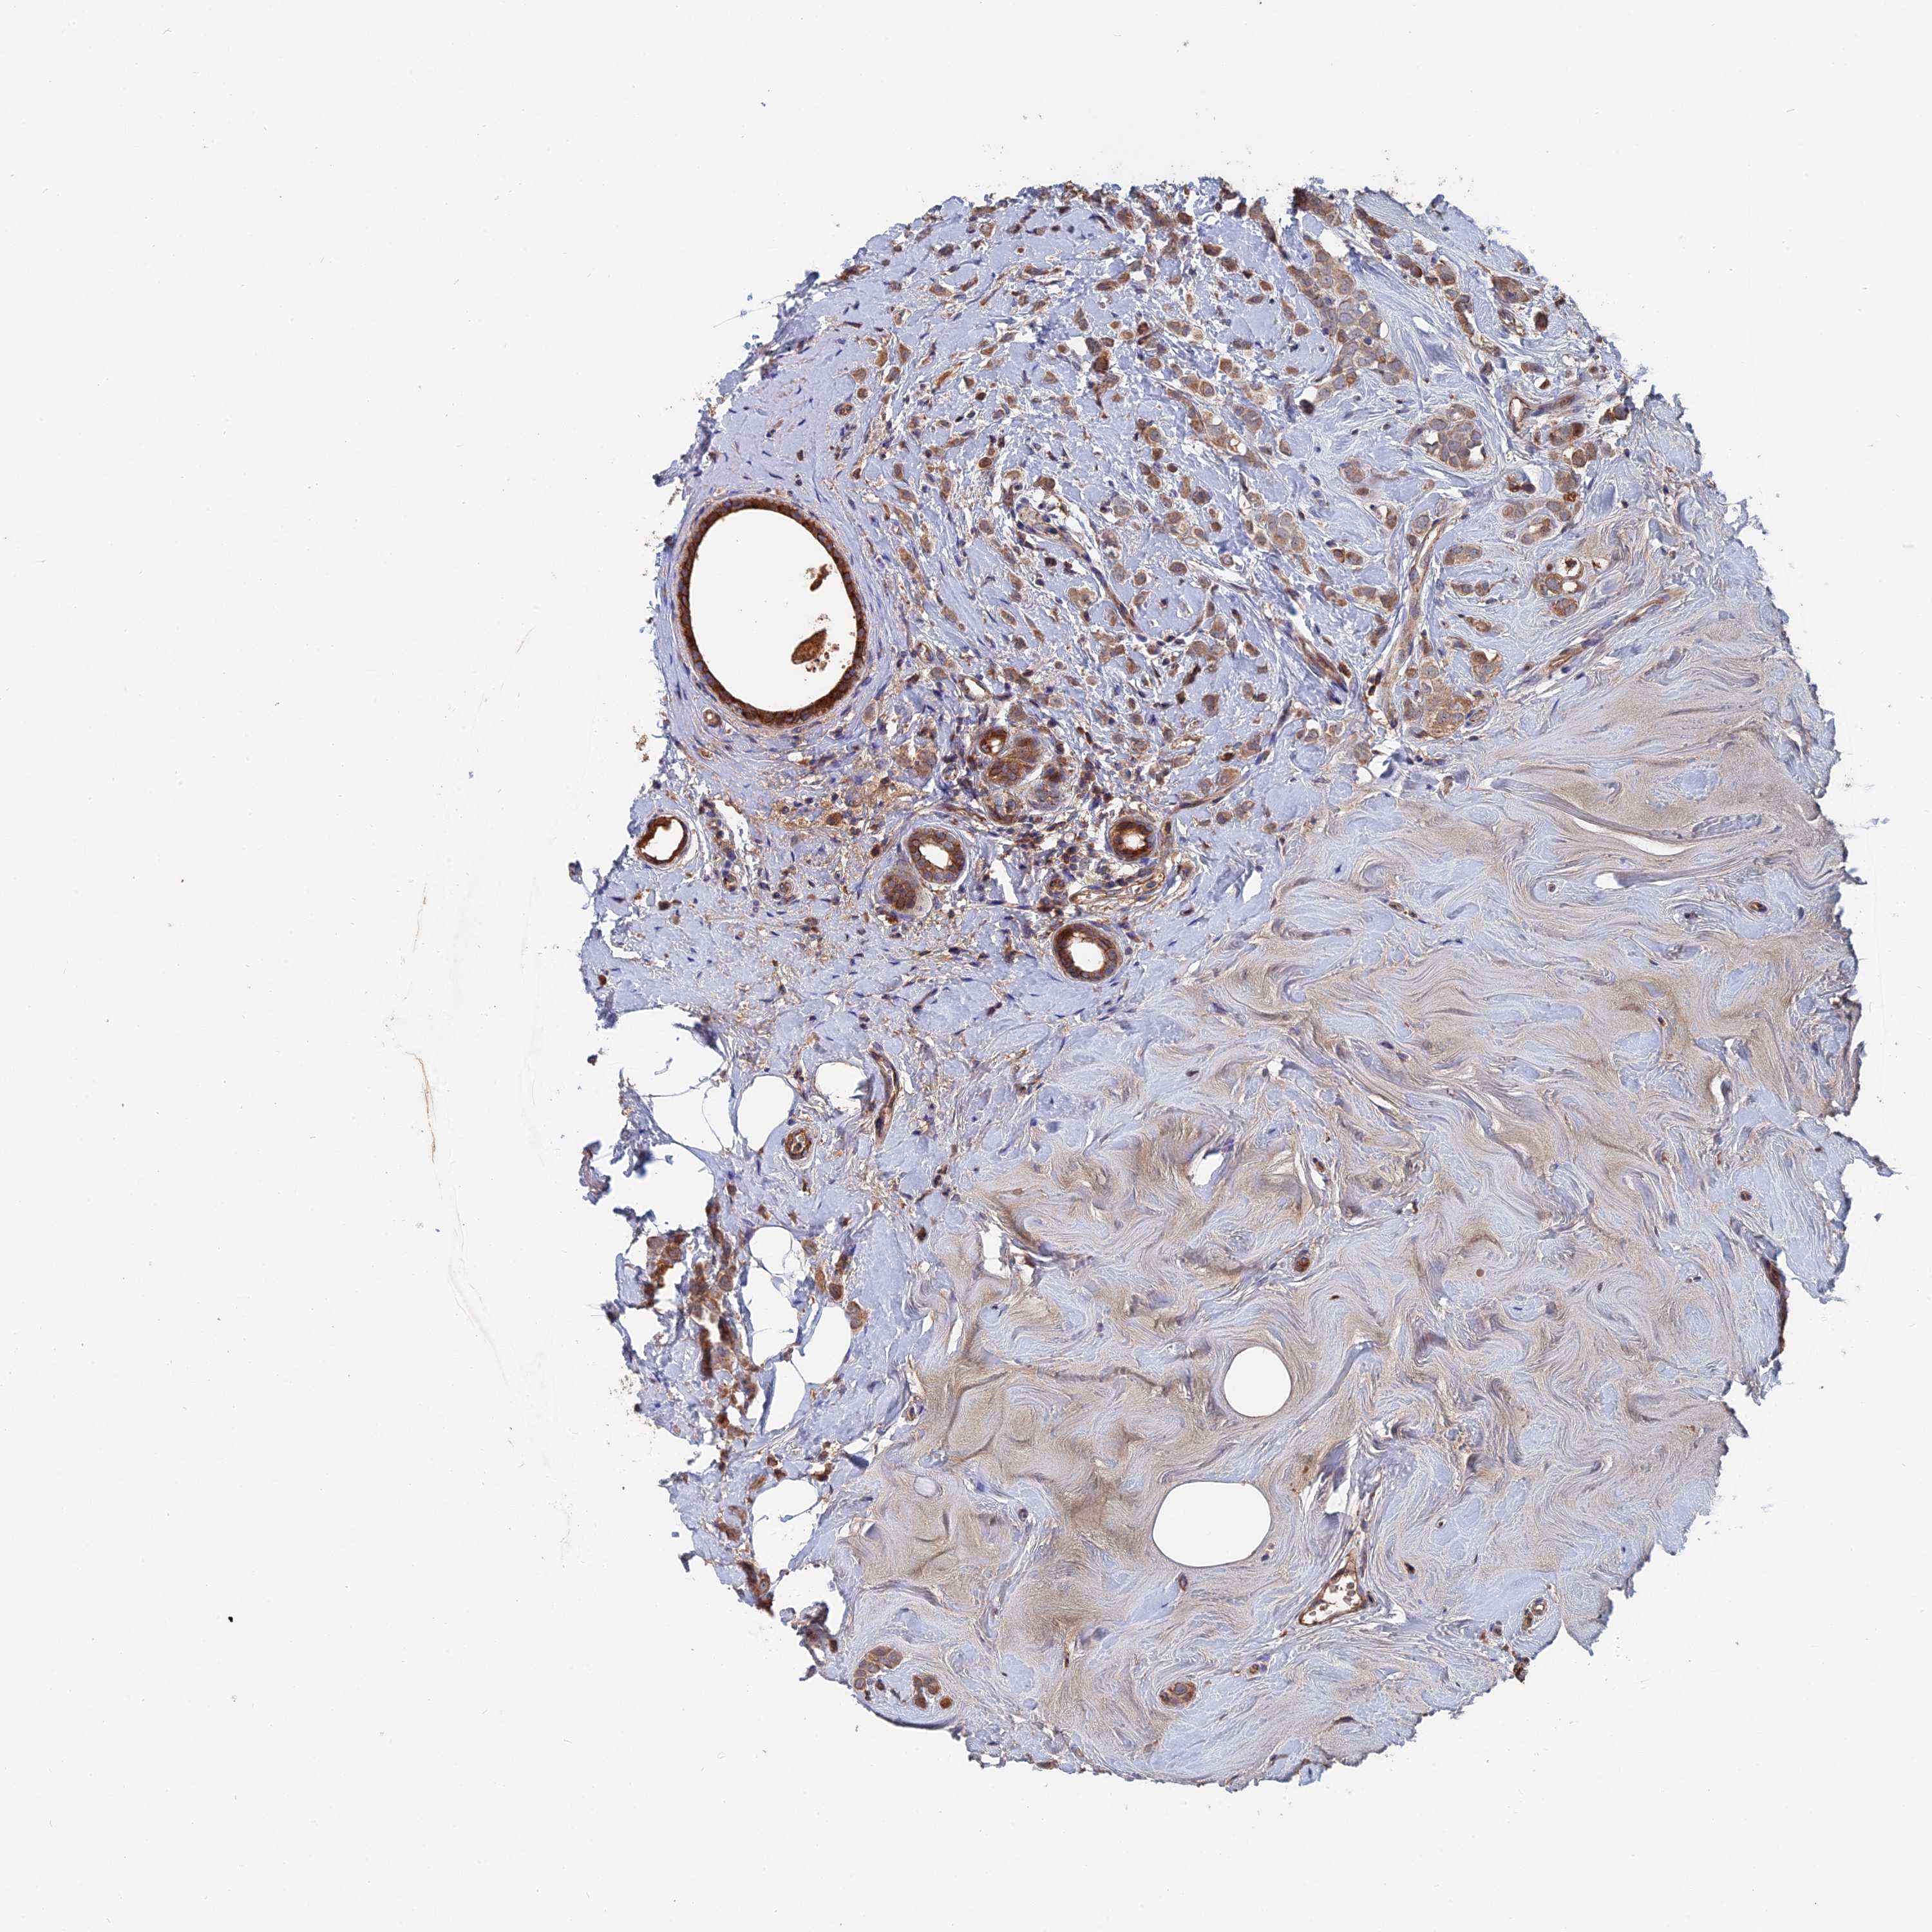

CANCER BREAST CANCER Show tissue menu

BRCA TCGA BRCA VALIDATION PROTEIN EXPRESSION